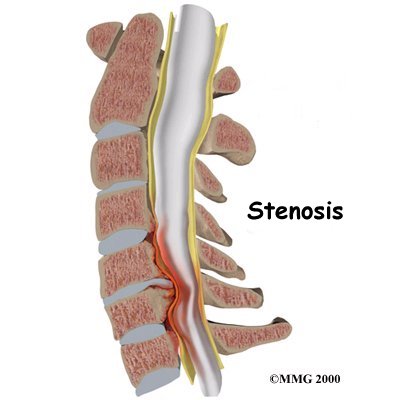

Spinal Stenosis (Cervical Myelopathy)

Stenosis means closed in. Spinal stenosis refers to a condition in which the spinal cord is closed in, or compressed, inside the tube of the spinal canal. Spinal stenosis may be caused by degenerative changes, such as bone spurs pushing against the spinal cord within the spinal canal.

Spinal Stenosis

However, stenosis can also develop when a person of any age has a disc herniation that pushes against the spinal canal. When the spinal cord is squeezed in the neck, doctors call the condition cervical myelopathy. This is an alarming condition that demands medical attention. Cervical myelopathy can cause problems with the bowels and bladder, change the way you walk, and affect your ability to use your fingers and hand.

Cervical Myelopathy